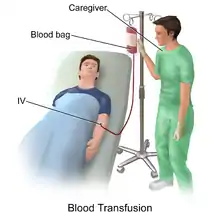

In transfusion medicine, transfusion-associated circulatory overload (aka TACO) is a transfusion reaction (an adverse effect of blood transfusion) resulting in signs or symptoms of excess fluid in the circulatory system (hypervolemia) within 12 hours after transfusion.[2] The symptoms of TACO can include shortness of breath (dyspnea), low blood oxygen levels (hypoxemia), leg swelling (peripheral edema), high blood pressure (hypertension), and a high heart rate (tachycardia).[3]

It can occur due to a rapid transfusion of a large volume of blood but can also occur during a single red blood cell transfusion (about 15% of cases).[2] It is often confused with transfusion-related acute lung injury (TRALI), another transfusion reaction. The difference between TACO and TRALI is that TRALI only results in symptoms of respiratory distress while TACO can present with either signs of respiratory distress, peripheral leg swelling, or both.[4] Risk factors for TACO are diseases that increase the amount of fluid a person has, including liver, heart, or kidney failure, as well as conditions that require many transfusions. High and low extremes of age are a risk factor as well.[5][6][7]

The management of TACO includes immediate discontinuation of the transfusion, supplemental oxygen if needed, and medication to remove excess fluid.[8]

Transfusion associated circulatory overload is prevented by avoiding unnecessary transfusions by following strict criteria necessitating blood transfusion, closely monitoring patients receiving transfusions, and transfusing smaller volumes of blood at a slower rate. Blood products are typically transfused at 2.0 to 2.5 ml/kg per hour but can be reduced to 1.0 ml/kg per hour for individuals at increased risk for TACO.[16] Patients susceptible to volume overload (e.g., renal insufficiency or heart failure) may be pre-treated with a diuretic either during or immediately following transfusion to reduce the overall net fluid balance.[8]

If TACO is suspected, the transfusion is stopped immediately and the patient is sat upright to prevent the fluid from backing up into the lungs. Treatment is two-fold: respiratory support and removal of excess fluid.[8] Patients with respiratory distress and/or hypoxemia are given supplemental oxygen or ventilatory support (through non-invasive or mechanical ventilation, if needed). To remove the excess fluid, patients are given diuretic therapy and their urine output is closely monitored to quantitate the amount removed.